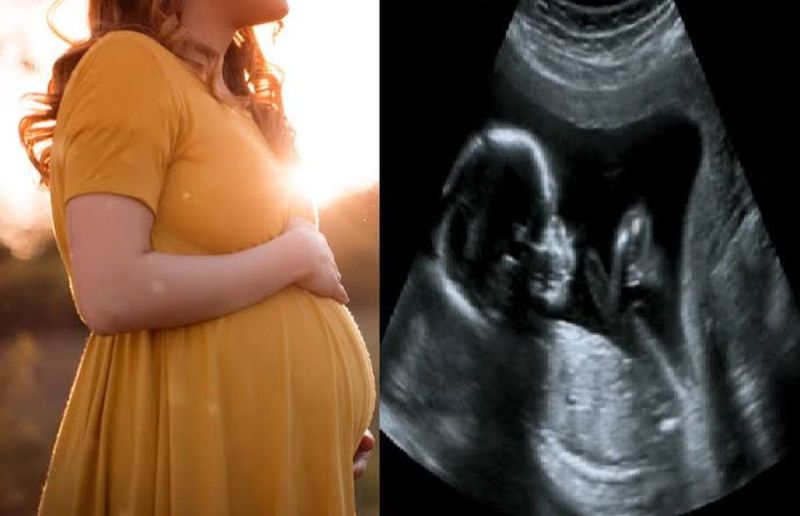

मातृ मृत्यु में अचानक वृद्धि से संबंधित मृत्यु लेखापरीक्षा रिपोर्ट में विशेषज्ञ समिति ने भविष्य में होने वाली मौतों को रोकने और स्वास्थ्य सेवाओं की गुणवत्ता में सुधार के लिए 27 सिफारिशें दी हैं।

स्वास्थ्य मंत्री दिनेश गुंडूराव ने कहा, सेवा प्रदाता और माता या परिवार की सुविधा के लिए अनावश्यक सिजेरियन नहीं करने सहित इन सिफारिशों में क्षमता निर्माण, उपकरणों और दवाओं के साथ सुविधाओं को मजबूत करना, रक्त भंडारण इकाइयों को मजबूत करना, सामान्य जन्म के बाद 3 दिन और सिजेरियन ऑपरेशन के बाद 7 दिन तक अस्पताल में रहना अनिवार्य करना शामिल है। प्रसव के स्थान के संबंध में जन्म योजना गर्भवती महिलाओं और परिवार के सदस्यों के साथ बनाई जानी चाहिए। सूची को संबंधित सुविधाओं के साथ साझा किया जाना चाहिए ताकि जटिलताओं के लिए तैयार रहा जा सके।

समिति ने पहली तिमाही सहित सभी एएनसी यात्राओं में उच्च जोखिम वाले कारकों के लिए सभी गर्भवती महिलाओं की जांच करके प्रसवपूर्व देखभाल की गुणवत्ता में सुधार करने, दिशा-निर्देशों में सुझाई गई खुराक के अनुसार आयरन और कैल्शियम की गोलियां उपलब्ध कराने, एनीमिया, रक्तचाप और रक्त शर्करा की निरंतर निगरानी करने और गर्भावस्था के दौरान एचआइवी, तपेदिक, हेपेटाइटिस, सिफलिस और स्पर्शोन्मुख बैक्टीरियुरिया जैसे संक्रमणों का पता लगाने की सिफारिश की है।

समिति के अनुसार मेडिकल कॉलेज अस्पतालों और जिला अस्पतालों में प्रसूति ओपीडी की देखरेख वरिष्ठ संकाय या वरिष्ठ प्रसूति विशेषज्ञों की जिम्मेदारी होनी चाहिए। गुणवत्तापूर्ण एएनसी प्रावधान के लिए आवश्यक उपकरणों जैसे बीपी उपकरण, वजन मशीन, रेडिएंट वार्मर, ग्लूकोमीटर और हीमोग्लोबीनोमीटर का अंशांकन सुविधा के प्रशासनिक चिकित्सा अधिकारी को सुनिश्चित करनी चाहिए।